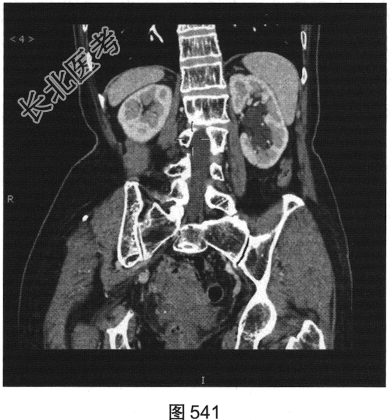

- 多项选择题3.[提示]CT平扫+增强(图538~图542)所见:双侧肾盂肾盏旁可见沿肾盂肾盏走行的多发囊样低密度灶, 未见明显强化。应考虑的鉴别诊断为( )

- 多项选择题4.综合影像表现,考虑肾盂旁囊肿的可能, 还应关注下列哪些情况( )

A、有无出血

B、有无感染

C、有无腹部其他脏器囊肿

D、肾实质受压情况

E、有无结石

F、有无并发肿瘤